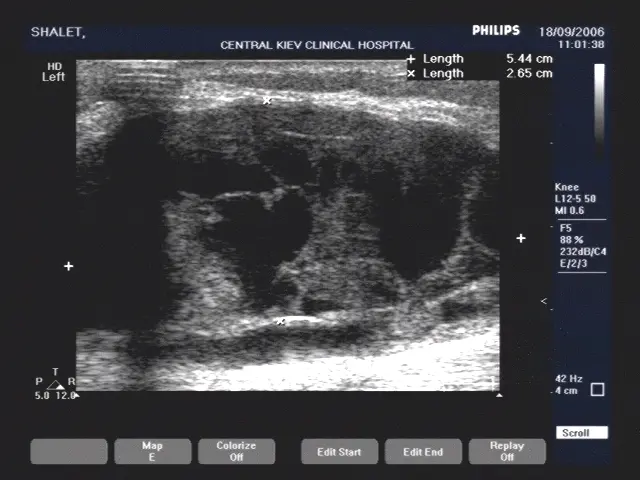

УЗД коліна — достатньо точний метод діагностики патології м’ягких тканин суглоба. УЗД дозволяє бачити запалення, уточнювати стан синовіальнї оболонки, об’єм рідини в коліні, її локалізацію і ті.

Проліферація синовіальної оболонки коліна при кісті Бейкера (фото нижче)

Оцінка кровотоку в синовіальній оболонці колінного суглоба